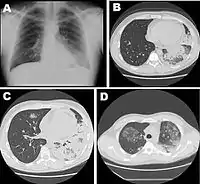

Рентгенологічні зміни в легенях при хворобі легіонерів — однобічна, двобічна дольова і вогнищева пневмонія. У більшості випадків уражені нижні долі, особливо правої легені. У деяких хворих має місце мігруюча пневмонія, що виникає в місцях старих інфільтратів. Водночас можлива поява і нових інфільтратів на раніше не уражених ділянках, часто в іншій легені. У третини хворих виявляють рентгенологічно лише явища плевриту. Поліпшення рентгенологічної картини в легенях починається з 12—14 дня хвороби, проте, остаточне відновлення затягується до 8—10 тижнів.